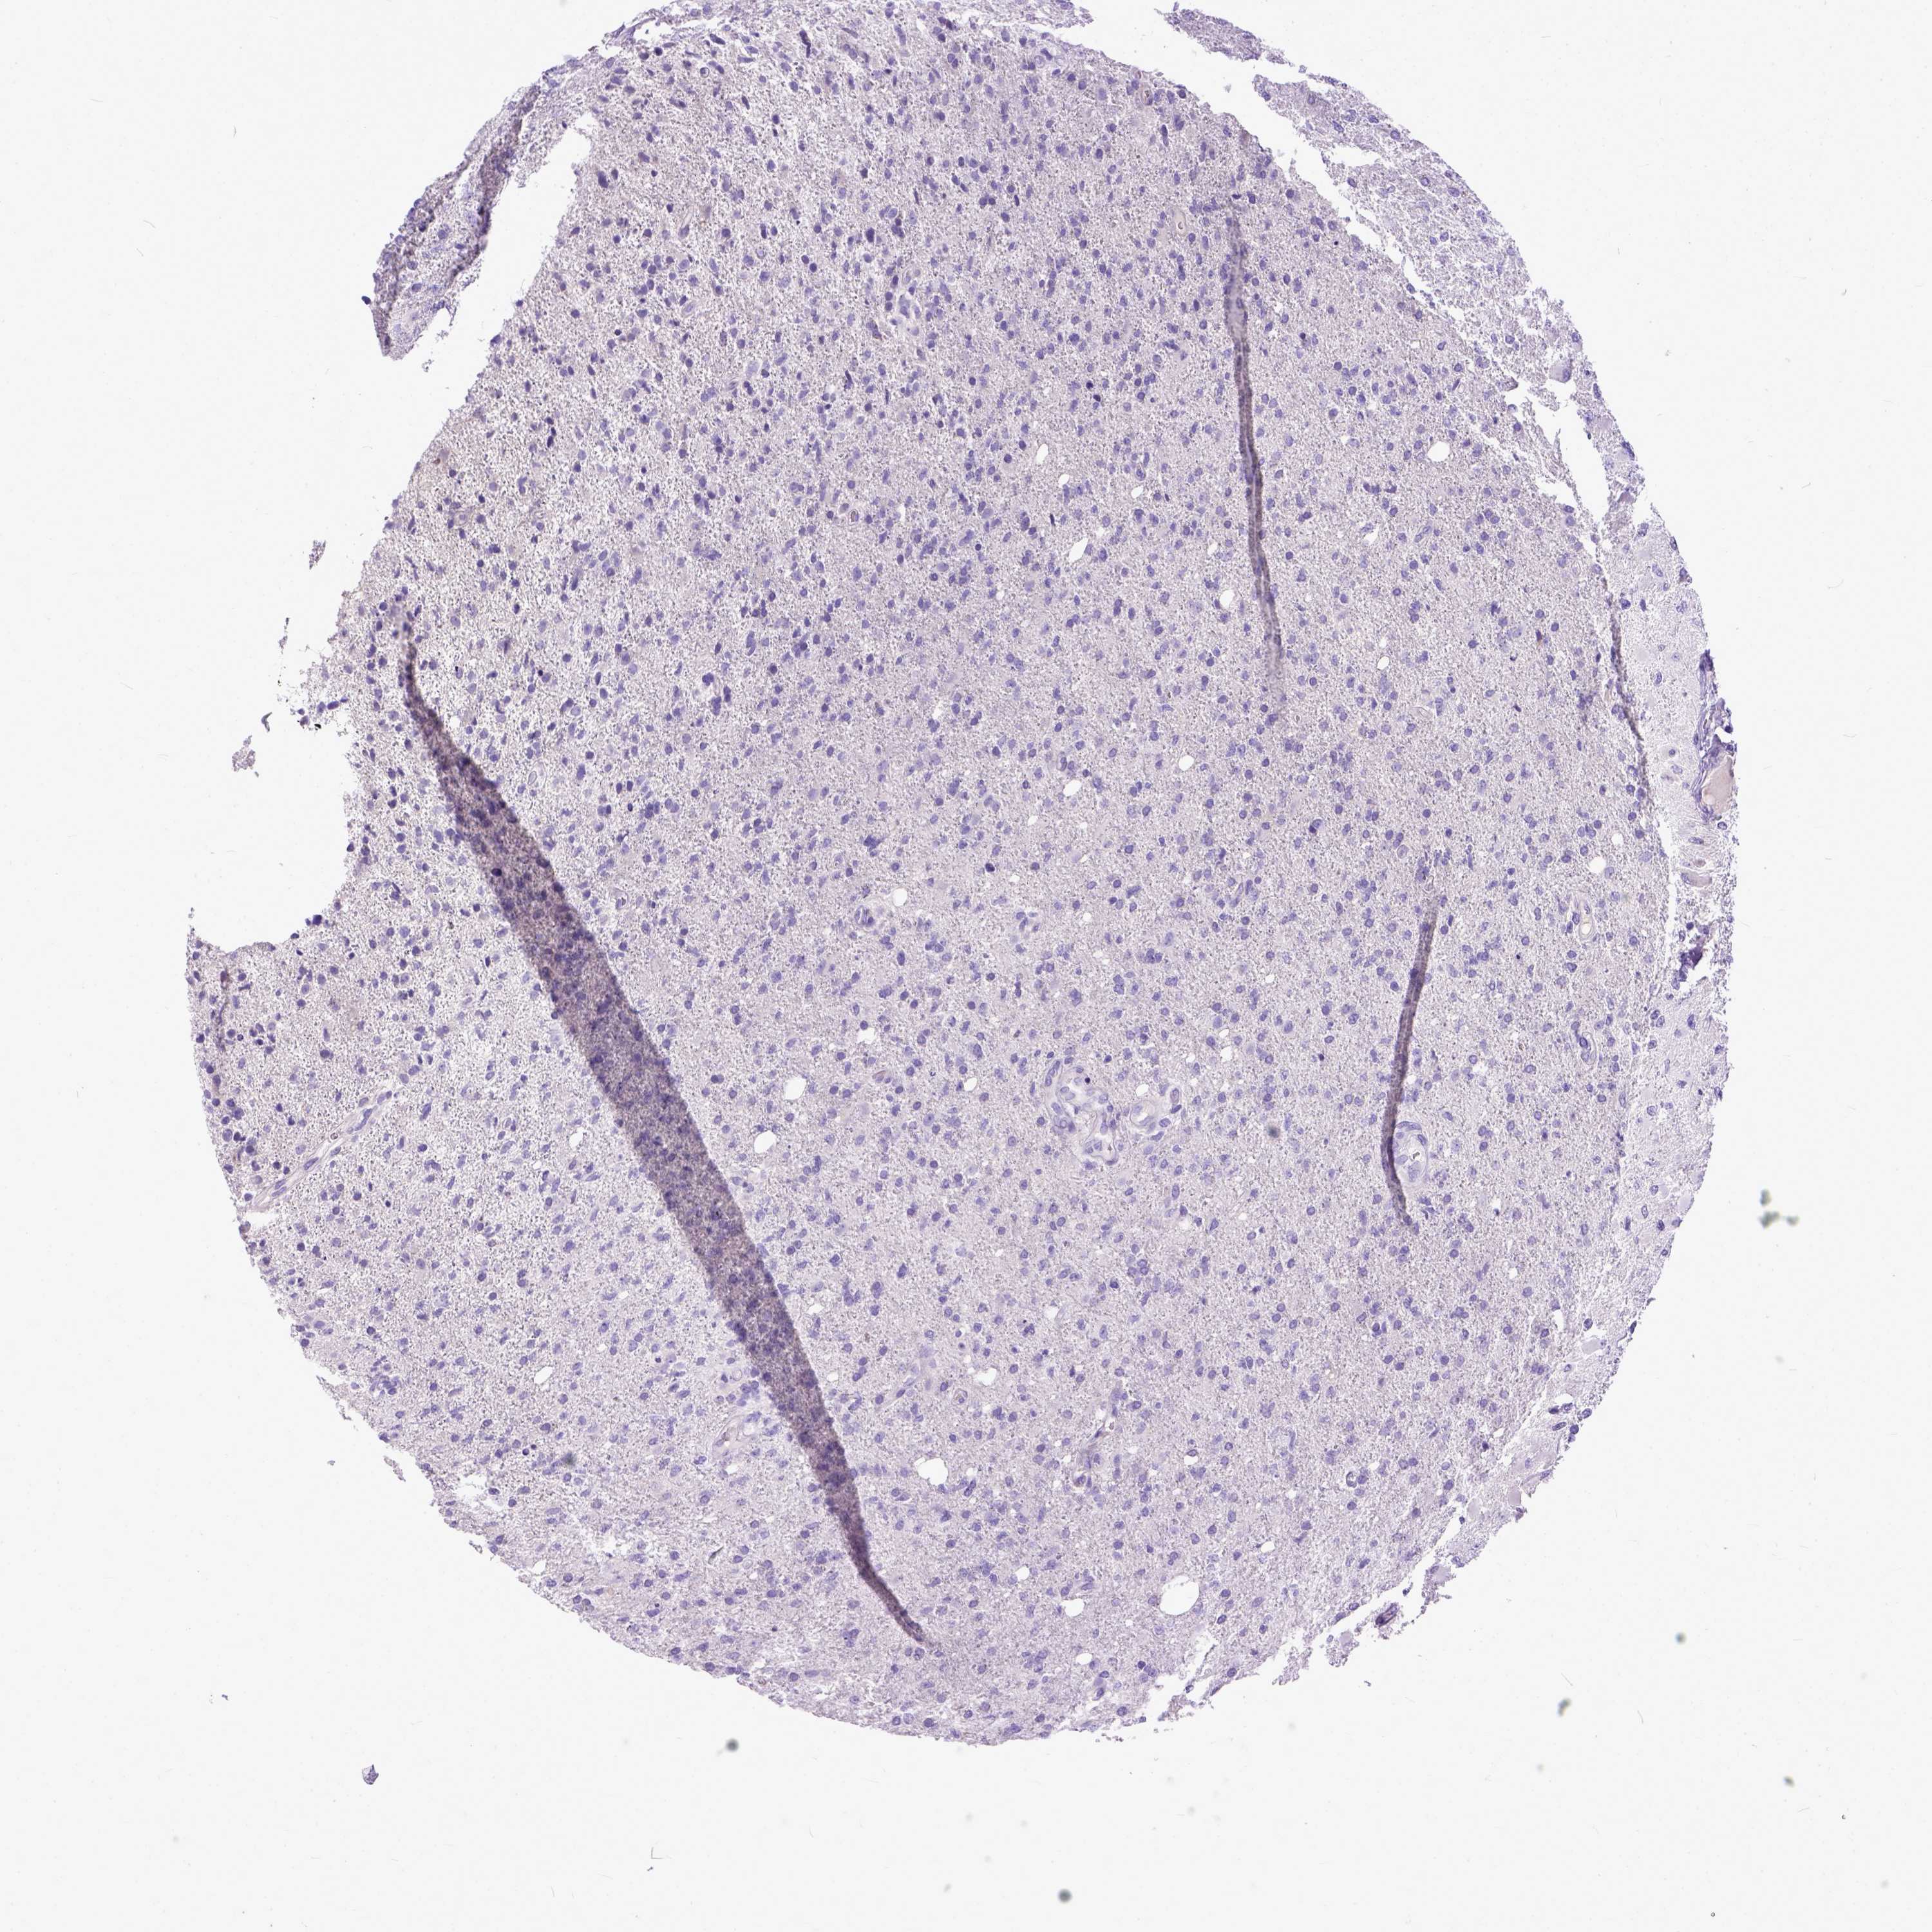

GLIOMA - Protein expressioni

A mouse-over function shows sample information and annotation data. Click on an image to view it in a full screen mode. Samples can be filtered based on level of antibody staining by selecting one or several of the following categories: high, medium, low and not detected. The assay and annotation is described here.

Note that samples used for immunohistochemistry by the Human Protein Atlas do not correspond to samples in the TCGA dataset.

Antibody stainingi

Antibody staining in the annotated cell types in the current human tissue is reported as not detected, low, medium, or high, based on conventional immunohistochemistry profiling in selected tissues. This score is based on the combination of the staining intensity and fraction of stained cells.

Each image is clickable and will lead to virtual microscopy that enables deeper exploration of all samples and also displays staining intensity scores, fraction scores and subcellular localization as well as patient and tissue information for each sample.

Antibody HPA035024

Staining

High

Medium

Low

Not detected

Intensity

Strong

Moderate

Weak

Negative

Quantity

>75%

75%-25%

<25%

None

Location

Nuclear

Cytoplasmic/membranous

Cytoplasmic/membranous,nuclear

Glioma, malignant, Low grade

Glioma, malignant, High grade